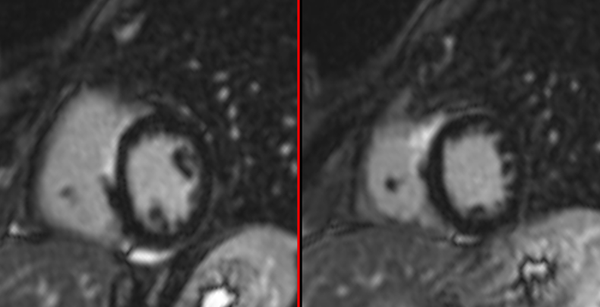

Amyloidosis